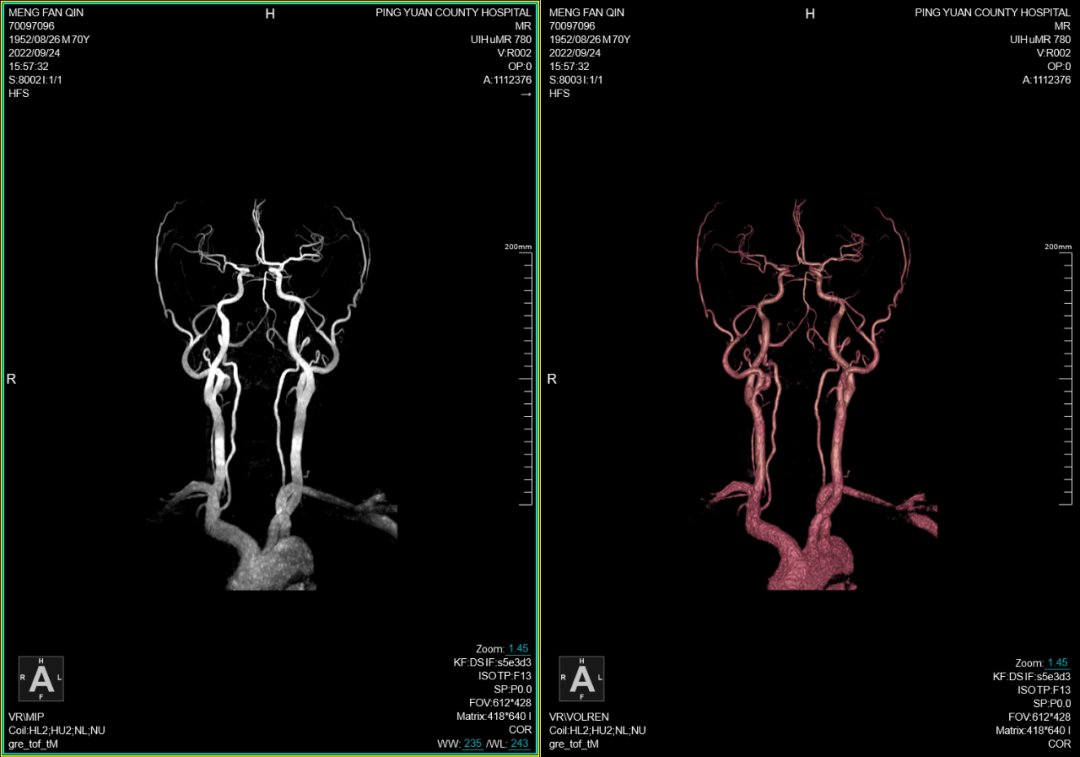

一、在颈部及颅脑血管检查方面优势明显,磁共振血管成像(MRA)为无创性检查方法之一,无电离辐射,无需或仅需少量造影剂(磁共振造影剂为钆剂,比CT的碘剂更安全),图像直观,尤其是3T磁共振的MRA图像质量更趋完美,目前已在不少领域完全取代了诊断性常规血管造影,其应用范围几乎遍及全身所有血管(如:脑动脉、颈动脉、胸腹主动脉、肾动脉和门静脉等)。

联影磁共振怎么样平原县第一人民医院联影uMR780 光梭3.0T磁共振正式投入使用,开启医学影像新时代!_https://www.jmylbn.com_新闻资讯_第5张

联影磁共振怎么样平原县第一人民医院联影uMR780 光梭3.0T磁共振正式投入使用,开启医学影像新时代!_https://www.jmylbn.com_新闻资讯_第6张